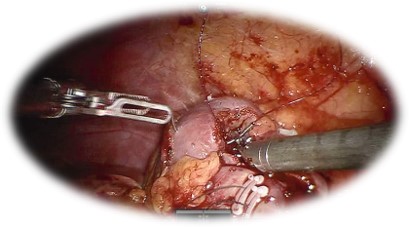

Nefrectomia parțială robotică:

• Presupune îndepărtarea procesului tumoral cu păstrarea parenchimul renal sănătos

• Oferă:

• Spitalizare scurtă, cu reintegrare socio- profesională rapidă

• Sângerare redusă

• Risc scăzut de complicații intra/ postoperatorii

• Comparativ cu chirurgia laparoscopică, abordul robotic permite scăderea timpului de ischemie.